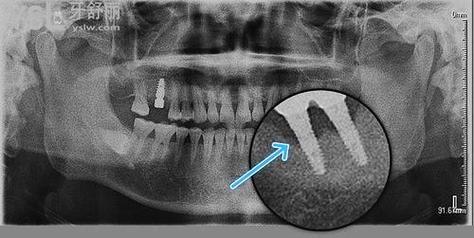

- 邻牙牙根吸收:极少数情况下,种植手术可能损伤邻牙牙根(如种植体位置过近),导致牙骨支持不足,引发倾斜。

- 种植体位置偏差:若种植体植入时过于靠近邻牙牙根,可能压迫牙根或导致骨吸收,引发邻牙倾斜。

- 种植体位置规划:保持与邻牙牙根至少1.5mm安全距离,避免邻侧骨板穿孔。